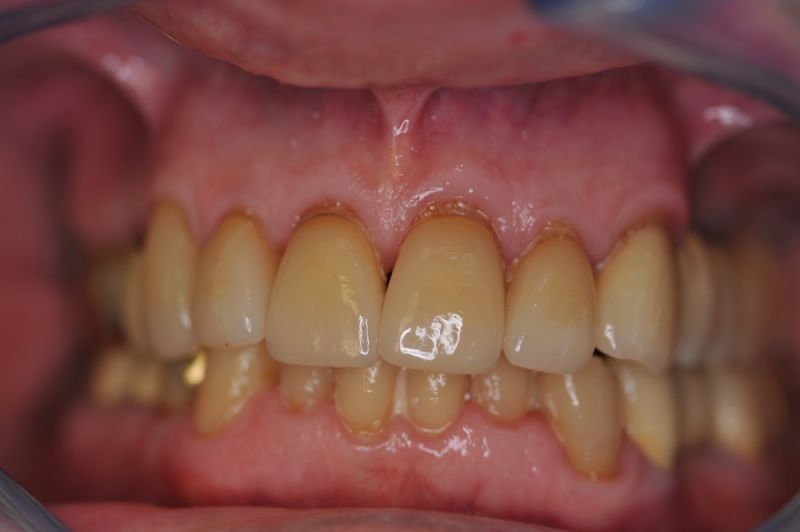

Rekonstruierter Kieler Patient im Recall

Die funktionstherapeutische Rekonstruktion befindet sich seit 17 Jahren im Munde des Patienten.

Gemeinsam ist man der Auffassung, dass sich heute zum Glück auszahlt, dass man beizeiten die Fundamente im Mund geschaffen hat, von denen der Patient heute im Alter zehrt.